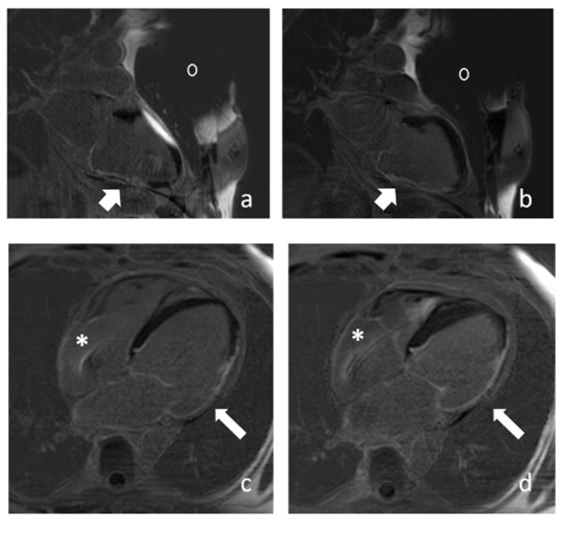

Fig. 3: Patient with ICD. a) LGE, 2CH-view. The anterior wall is covered by an hyperintensiv artifact b) WB-PSIR-LGE suppresses this artifact. c) LGE, 4CH and d) WB-PSIR LGE show comparable image quality. Arrow: myocardial scar. Asterisk: lead artifact. 0: device artifact. |